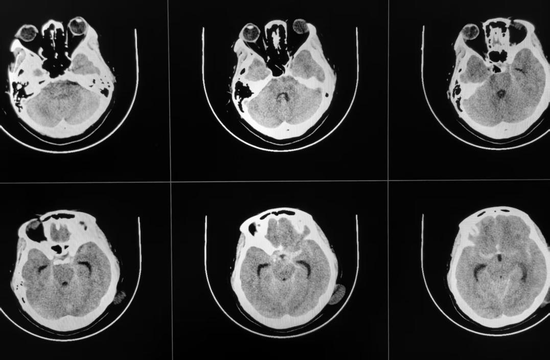

王女士(化名)因突发头痛伴恶心、呕吐5小时被紧急送往我院就诊,入院时症状不断加重,意识逐渐模糊,且频繁恶心、呕吐,急诊头颅CT检查显示蛛网膜下腔出血。脑科医院院长纪文军主任医师接诊后,立即启动卒中绿色通道。经详细问诊,得知王女士有多年的肾病综合征及高血压病史,且血压一直居高不下,动脉瘤破裂风险极高。纪文军主任医师判断情况危急,立即安排脑血管检查进一步明确诊断。

术前CT提示蛛网膜下腔出血